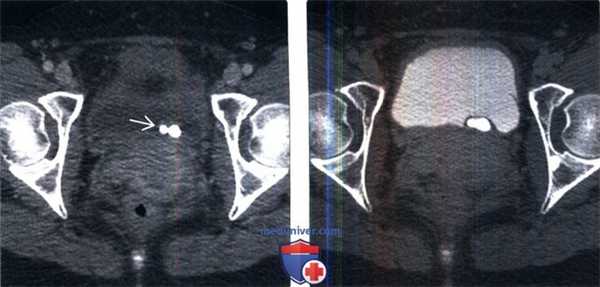

(Левый) На аксиальной КТ-урограмме через малый таз визуализируется удвоенная система левой почки, мочеточник верхней лоханки оканчивается уретероцеле? содержащим конкременты. Мочеточник нижней лоханки не расширен и прикрепляется рядом с уретероцеле. Обратите внимание на простатическое вдавление в основании мочевого пузыря.

(Правый) На 3D-peконструированном MIP изображении КТ урограммы (вид сзади) визуализируется удвоенная чашечно-лоханочная система левой почки с конкрементами в лоханочно-мочеточниковом сегменте и уретероцеле верхней лоханки.

(Слева) КТ мочевого пузыря без контрастирования, аксиальный срез: два плотных кальцинированных конкремента в области левого МПС.

(Справа) Аксиальная проекция того же среза, полученная в отсроченную урографическую фазу: конкременты находятся внутри уретероцеле. Иногда дифференциальная диагностика между врожденным уретероцеле, содержащим камни и приобретенным расширением терминального отдела мочеточника при обструкции конкрементом (так называемое «певдоуретероцеле») может представлять трудность.